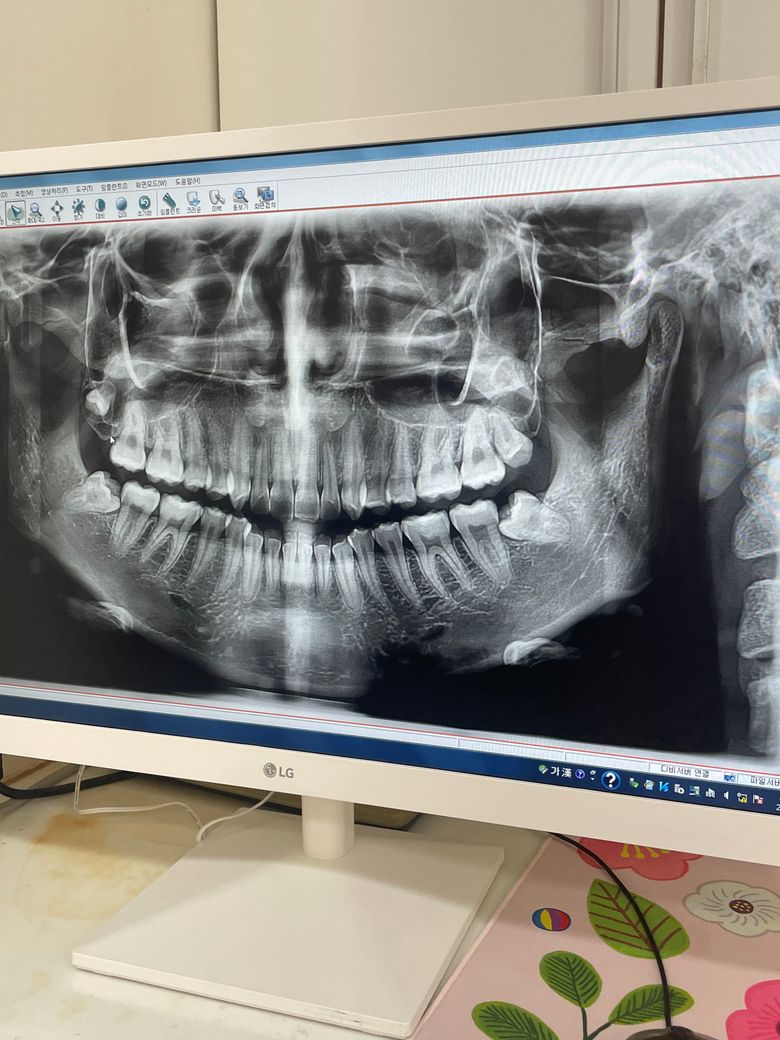

사랑니가 어금니랑 떨어져서 났어요 발치해야하나요?

제 위쪽 왼쪽 사랑니가 어금니랑 떨어져서 이상한 방향으로 자랐습니다 저 엑스레이는 옛날 사진이고 지금은 다 자란 것 같아서 잇몸을 뚫고 나왔습니다. 현재 어떤 상황이냐면 어금니랄 사랑니가 붙어있지 않고 어금니가 있고 잇몸이 있고 저 사랑니가 있어요.. 이거 발치해야하나요? 발치 할 수 있나요?

사랑니가 비스듬하게 맹출되어 잇어서 관리가 안되면 염증이 생기고 앞치아에 안좋게 작용할수가 잇으니 발치를 하시는게 좋을것같습니다 .

저 엑스레이 상 사랑니는 다 자라지 않았습니다 그래서 점차 자라면서 잇몸을 뚫고 아래로 내려와 맹출한 것이고요 지금 관리잘되고 불편감이 없다면 굳이 뽑을 필요는 없으나 딱히 기능하는 어금니도 아니라 빼셔도 무방합니다

현재 사랑니 각도가 기울어 있어 방치를 하는 경우에는

비정상적으로 자란 사랑니가 어금니를 밀거나 눌러 주변 치아를 손상시킬 가능성이 높기에 발치가 필요로 됩니다.

매복사랑니는 잇몸을 절개하여 발치가 가능하나 난이도가 높기에 구강악안면외과 전문의를 방문하여 정밀한 엑스레이 검사를 받고 현재 상황에 대한 정확한 상태 확인후 사랑니 발치를 하길 권합니다.